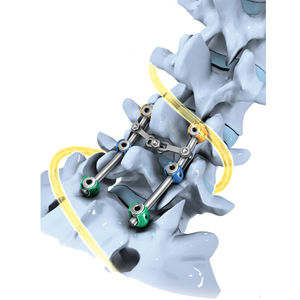

... ARTRODESIS CERVICAL EN ADULTOS Y DEFORMIDADES PEDIÁTRICAS DE LA COLUMNA VERTEBRAL El sistema de osteosíntesis KM BABY está destinado a proporcionar fijación entre dos o más vértebras. Indicaciones ADULTOS : - Artrodesis ...